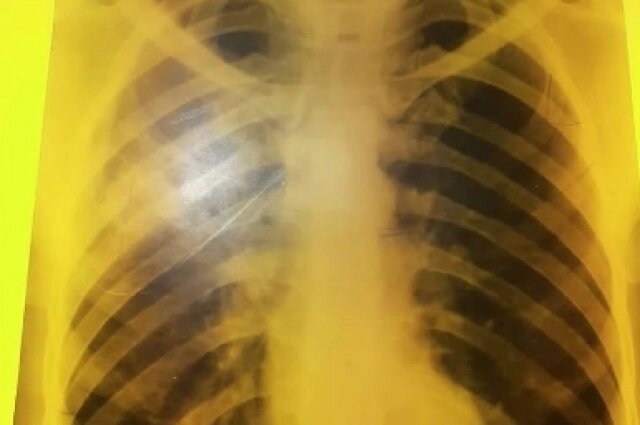

Будущий врач оказалась в роли пациента. «Инфильтративный туберкулез левого легкого, первого и второго сегмента, в стадии распада», такое заключение вынесли ей в диспансере.

«Для работы с юными пациентами после болезни нужно сделать операцию, чтобы минимизировать рецидив. Сейчас у меня в легких фиброз, но он никак не мешает. А хирургическое вмешательство не гарантия того, что болезнь не вернется. Да и допустят ли меня после операции к детям тоже большой вопрос», — делится Мария.